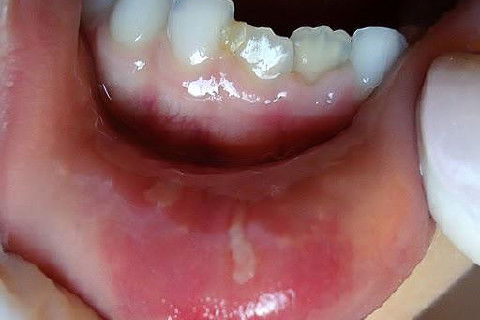

Menino de 6 aninhos sofreu um traumatismo ontem na hora do recreio, lá na escolinha aonde atendo, bateu a boquinha na mesa na hora do lanche.

Examinei-o e constatei ter sofrido apenas uma concussão.

CONCUSSÃO é o trauma dentário menos agressivo que se apresenta.

Sem consequências aparentes ao exame clínico, nenhum dano ao tecido dentário, com pequena agressão aos tecidos de suporte e os dentes apresentam pequena sensibilidade ao toque.

Obs: As duas últimas fotos foram tiradas hoje (24 hs depois).

Fotos do caso